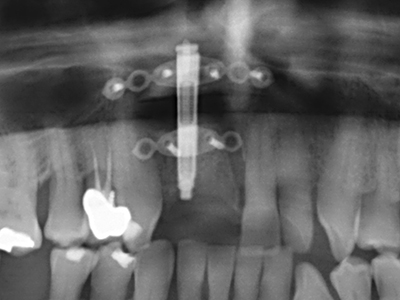

La preparación de la ventana lateral en la elevación del suelo del seno maxilar representa un enorme reto, sobre todo para profesionales de la implantalogía que tienen poca experiencia en técnicas quirúrgicas. Retirar la cobertura ósea del seno maxilar sin provocar daños en la membrana de Schneider es tan solo una parte de la operación; tras crear un acceso suficiente, es preciso movilizar con cuidado la mucosa del seno maxilar a fin de dejar espacio para el material o los implantes que vayan a incorporarse. En esta aplicación la cirugía piezoeléctrica resulta útil en dos sentidos: por un lado, el uso de insertos diamantados permite realizar una retirada selectiva del hueso y, si se actúa con cuidado, la membrana permanece intacta, y por otro lado, las frecuencias de ultrasonidos favorecen también un desprendimiento sin problemas de la membrana, pues se transfieren al espacio comprendido entre la mucosa y el suelo del seno maxilar gracias al uso de piezas romas especiales (Cassetta, Ricci et al. 2012, Pereira, Gealh et al. 2014) (Rickert, Vissink et al. 2013). De este modo, no es de extrañar los trabajos publicados en la actualidad sobre la técnica de elevación del suelo del seno maxilar mediante la técnica de Caldwell-Luc con instrumentos piezoeléctricos (Wallace, Tarnow et al. 2012).

En la cirugía del seno maxilar surgen otros campos de aplicación: En este punto, tras la preparación concéntrica de una tapa ósea de la pared del seno maxilar (que suele tener forma trapezoidal), es posible eliminar patologías y cuerpos extraños del seno maxilar. La tapa ósea se repone después de finalizar la parte intra-antral de la operación y se asegura frente a una posible dislocación mediante cuñas o suturas adaptables.